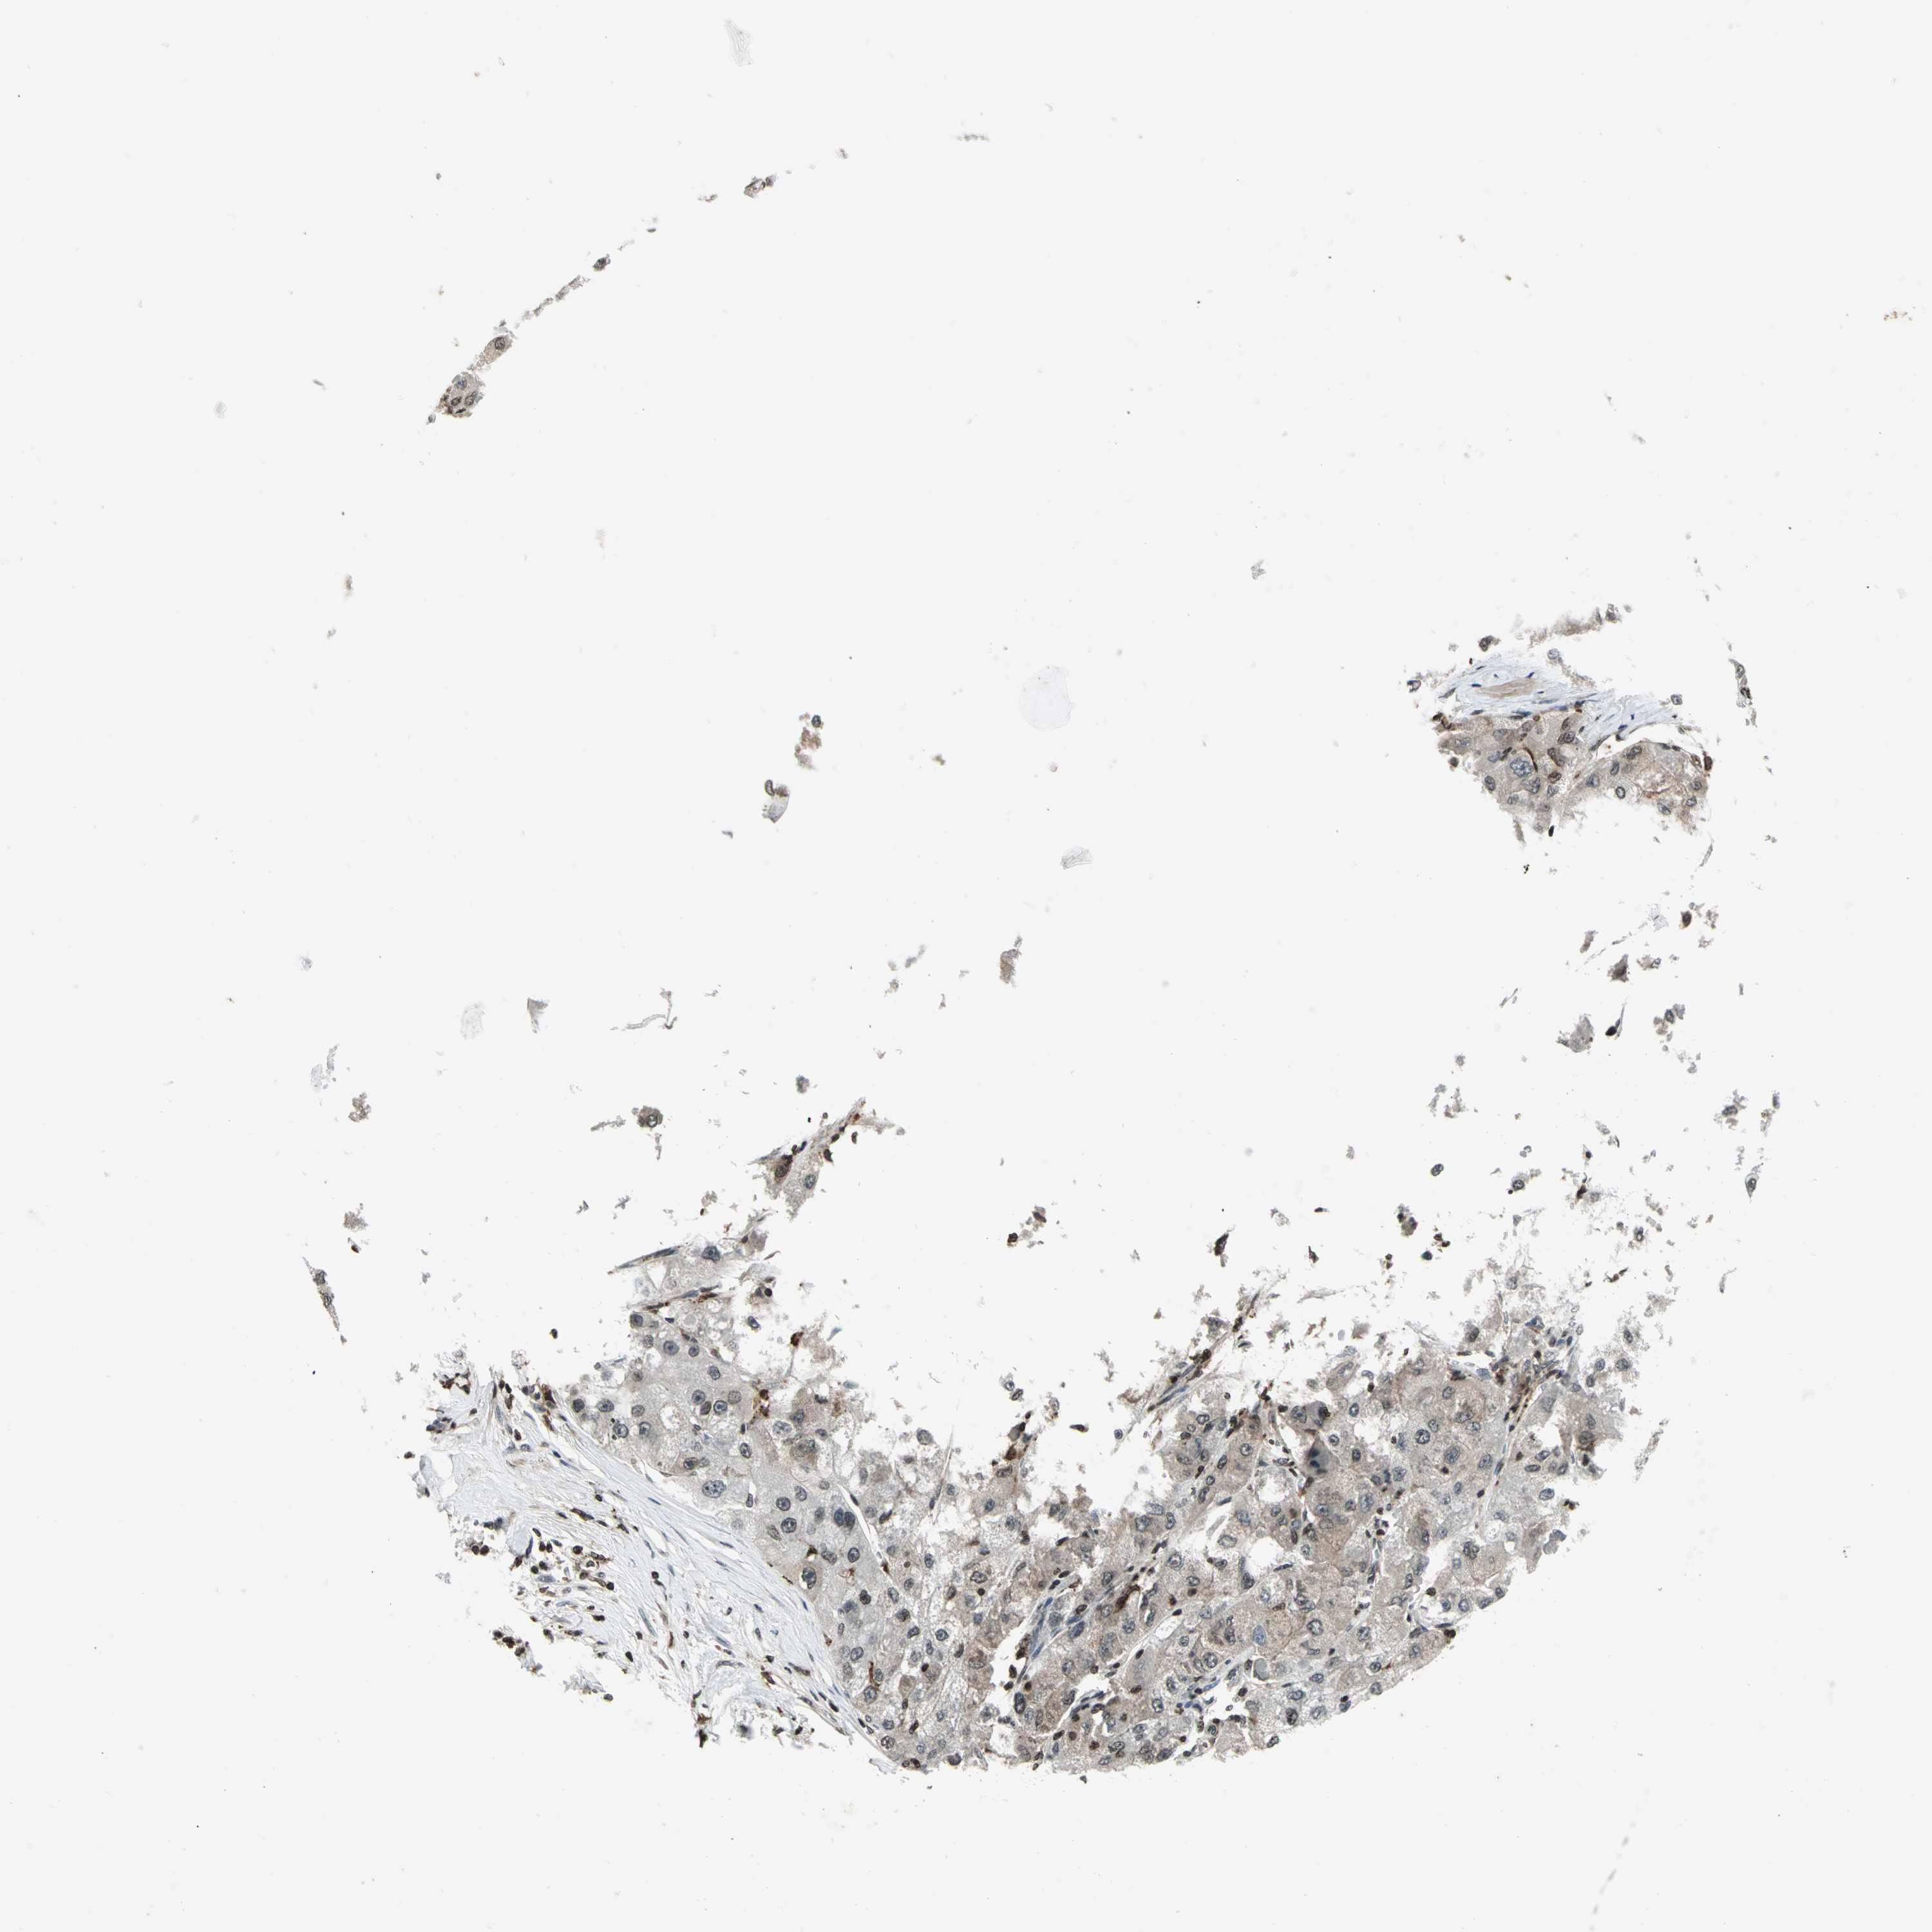

LIVER CANCER - Protein expressioni

A mouse-over function shows sample information and annotation data. Click on an image to view it in a full screen mode. Samples can be filtered based on level of antibody staining by selecting one or several of the following categories: high, medium, low and not detected. The assay and annotation is described here.

Note that samples used for immunohistochemistry by the Human Protein Atlas do not correspond to samples in the TCGA dataset.

Antibody stainingi

Antibody staining in the annotated cell types in the current human tissue is reported as not detected, low, medium, or high, based on conventional immunohistochemistry profiling in selected tissues. This score is based on the combination of the staining intensity and fraction of stained cells.

Each image is clickable and will lead to virtual microscopy that enables deeper exploration of all samples and also displays staining intensity scores, fraction scores and subcellular localization as well as patient and tissue information for each sample.

Antibody HPA003162

Antibody CAB005191

Staining

High

Medium

Low

Not detected

Intensity

Strong

Moderate

Weak

Negative

Quantity

>75%

75%-25%

<25%

None

Location

Nuclear

Cytoplasmic/membranous

Cytoplasmic/membranous,nuclear

Carcinoma, Hepatocellular, NOS

Cholangiocarcinoma